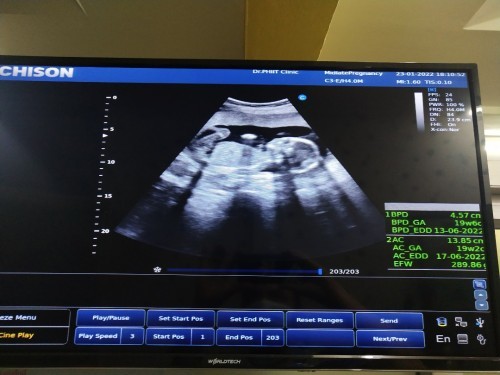

18 w จ้า #เพศชาย #ทีมมิ.ย

Post reply image